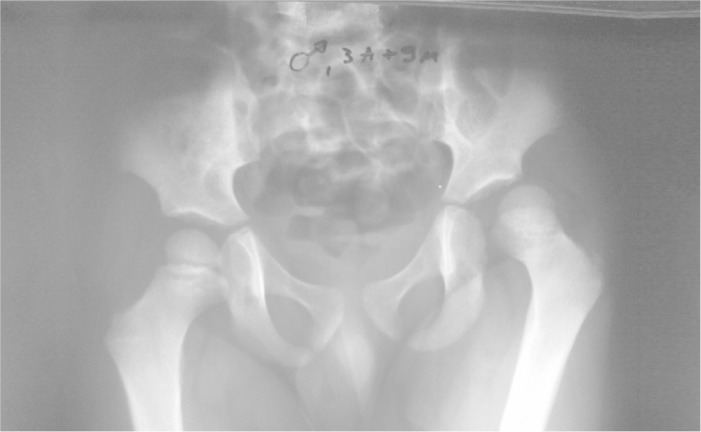

Figure 2A.

Radiographic appearance of traumatic posterior dislocation of the hip